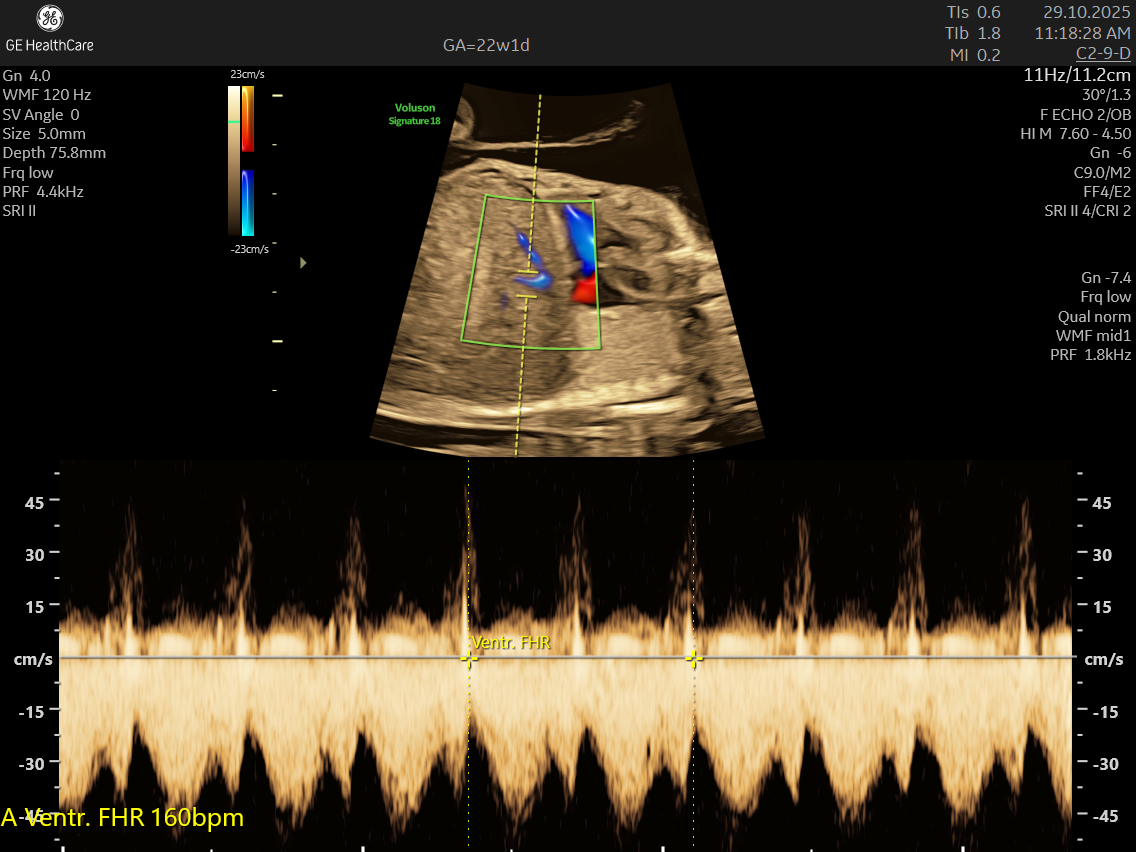

- Blood Flow Patterns: Detects arrhythmias or irregular heartbeats and checks for efficient circulation through the heart and major vessels.

- Arrhythmias like premature atrial and ventricular contractions, supraventricular tachycardia, and complete heart block.

- Abnormalities in blood flow patterns and valve function observed on Doppler imaging.